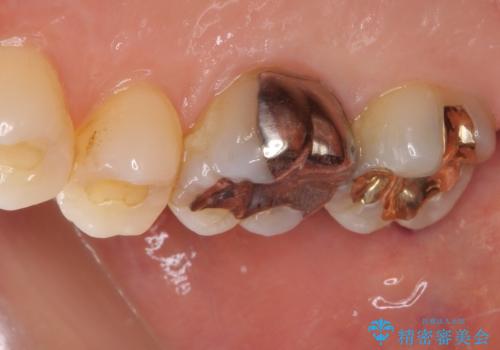

- 上の奥歯に装着されていた銀歯が外れてしまったとのことで来院された患者様です。

強い咬合力により銀歯と歯の間に隙間ができ、その隙間から虫歯となって外れてしまったと想像されました。

銀歯では歯と充填物の固さに違いがあり、再度外れてしまうリスクが高いため、固さが歯と近いゴールドインレー(PGAインレー)にて修復することとしました。